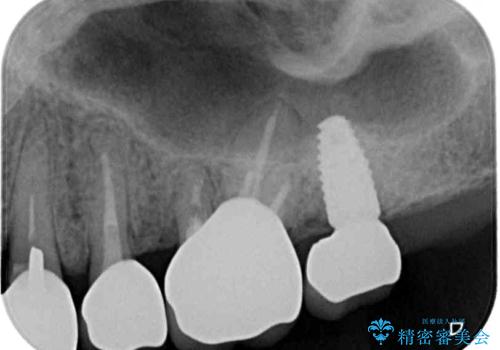

- 上下の奥歯が痛いとのことで来院された患者様です。

診察をしたところ、上下大臼歯の歯肉に排膿路認められたため、根管治療を行い、その後補綴治療を行うこととしました。

また、上顎の欠損部位にはインプラント治療を行うこととしました。

改めて診療を行ったところ、歯根破折が認められ、抜歯後にインプラント治療を行うこととしました。